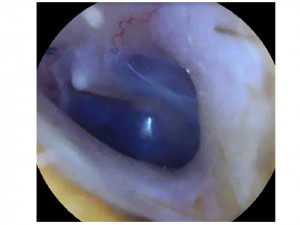

В процессе сурдопедагогического обследования выявлены минимальные расстройства слуховых функций. Игровая тональная аудиометрия: правое ухо – 17,5 дБ, левое ухо – 20 дБ.

Отоскопия приложена.

Скажите, пожалуйста, является ли представленная отоскопия слуховых проходов и барабанной перепонки нормативной?

Здравствуйте. По фото барабанные перепонки выглядят неостро изменёнными: признаков гноя, перфорации или выраженного воспаления не видно, но отмечается втянутость и изменение цвета, что может соответствовать хронической дисфункции евстахиевой трубы или последствиям перенесённых серозных отитов. Это не является строго нормой.